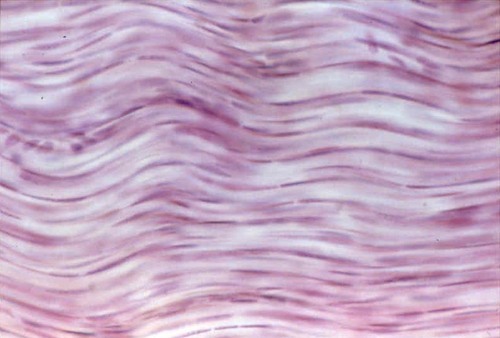

What kind of tissue is this?

Areolar connective tissue

Dense regular connective tissue